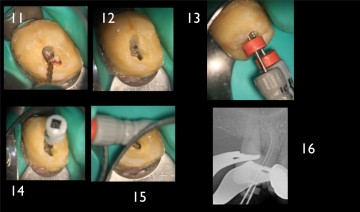

Initial x-ray, opening of the access cavity and x-ray with scouting file in the MB1 and MB2. The mineralization of the root canal entrance constrains the initial scouting.

The flaring instrument One Flare eliminates the first millimeters of the pulp parenchyma, thus reducing the stress on the files which are realigned in the root canal, in order to facilitate the access to and the shaping at the apical preparation limit.

The reasoned preparation of the root canal entrance with the flaring instrument One Flare allows for safe endodontic shaping and cleaning while preserving the root canal’s homothety.